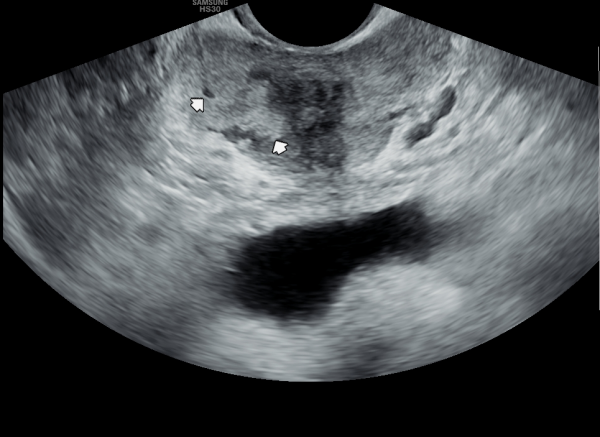

서울가정의학과의원에 첫 내원 당일 지난 5개월동안 회음부 통증과 배뇨장애로 타 비뇨기과 여러곳에서 치료를 했으나 증상의 호전이 없다고 내원 당일 검사한 경직장 전립선 초음파 검사상 사정관 입구의 석회화와 사정관의 섬유화 그리고 정낭의 낭종이 관찰되는 초음파 자료입니다.

On the first visit to Seoul Family Medicine Clinic, the patient reported having perineal pain and urination problems for the past five months, despite receiving treatment at several other urology clinics with no improvement.

A transrectal prostate ultrasound performed on the day of the visit showed calcification at the opening of the ejaculatory duct, fibrosis (scarring) of the duct itself, and cysts in the seminal vesicles.

또한 방광벽이 배뇨장애로 두꺼워져 과민성 방광이 의심되는 초음파 사진입니다.

The ultrasound image also shows that the bladder wall has become thickened, likely due to urination difficulties. This may suggest an overactive bladder, which can cause frequent or urgent urination.

내원 당일 경직장 전립선 초음파 검사상 오랜 세월동안 사정관의 벽이 수명을 다한 거짓 중층 원주 상피 세포가 탈락되어 사정관 입구에 막혀 두텁게 쌓여 있고 요도에도 탈락된 상피 세포가 쌓여서 정낭과 정관 그리고 전립선액 과 배뇨등의 순환 장애를 보이고 있는 경직장 전립선 초음파 사진입니다.

This transrectal prostate ultrasound image, taken on your first visit, shows that over many years, the wall of the ejaculatory duct has been blocked by a buildup of old, shed pseudostratified columnar epithelial cells. These cells have accumulated at the opening of the ejaculatory duct and in the urethra, leading to circulation problems in the seminal vesicles, vas deferens, and prostate fluid, as well as urinary flow issues.